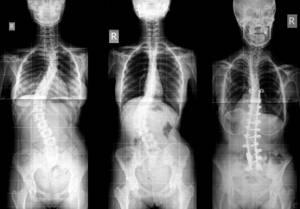

Basta con una simple radiografía para confirmar una escoliosis, recuerda que aparte de la desviación lateral, en una escoliosis las vértebras tienen que estar rotadas, si no lo están deberemos investigar dismetrías de las piernas, o si nos encontramos ante una escoliosis postural.

Con la radiografía podremos medir la angulación de la curva y realizando comparaciones con radiografías previas podremos saber si una escoliosis progresa. En la radiografía también podremos determinar la madurez ósea del niño/adolescente y de este modo determinar cuanto tiempo le queda de crecimiento, recuerda que una escoliosis deja de avanzar terminado el crecimiento.